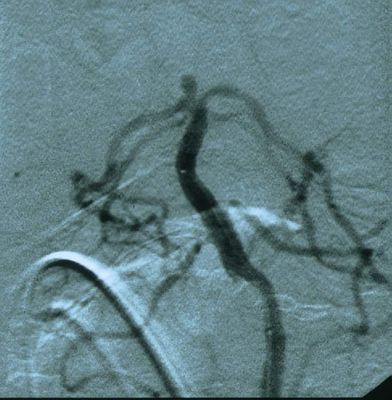

基底动脉顶端动脉瘤栓塞前